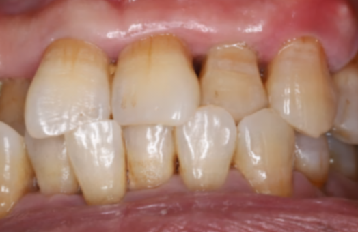

口内检查:全口牙龈轻度吸收,牙列不齐,12、22反合,口腔卫生一般。

主诉牙情况:22牙体颜色稍变暗,  松动 III 度,叩诊(-),牙 龈无红肿、溢脓、牙周袋 6mm,近远中龈乳头缺损。